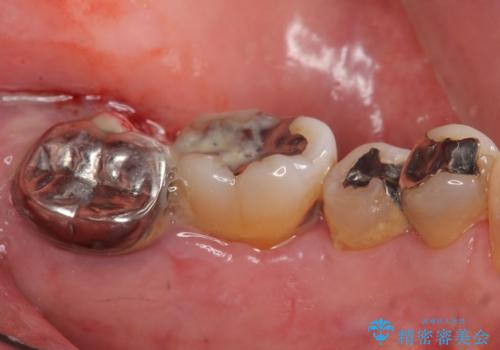

[MTMを行い歯の神経を保存] 歯周補綴ブリッジ

![[MTMを行い歯の神経を保存] 歯周補綴ブリッジの症例 治療前](https://seimitsushinbi.jp/wp/wp-content/uploads/2021/04/21310c2f37874ac2f2ba9939da2fee68-500x350.jpg?v=1618452125)

![[MTMを行い歯の神経を保存] 歯周補綴ブリッジの症例 治療後](https://seimitsushinbi.jp/wp/wp-content/uploads/2021/04/75330aaa19199048b71f28658fe46b5b-1-500x350.jpg?v=1618452202)